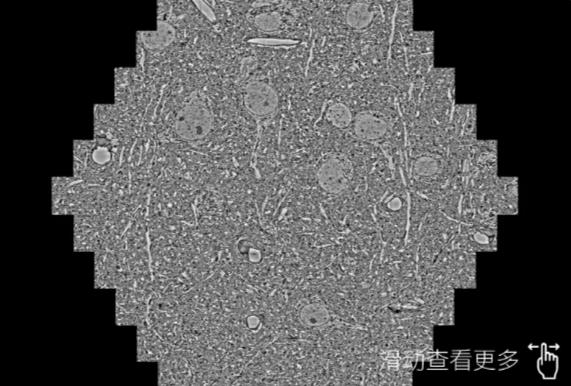

鼠脑切片。左图使用石家庄蔡司石家庄扫描电镜MultiSEM706对165μmx143pm面积区域成像,耗时仅需1.5秒。右图为鼠脑切片中30μm区域放大效果。样品由芝加哥大学B.Kasthuri提供。